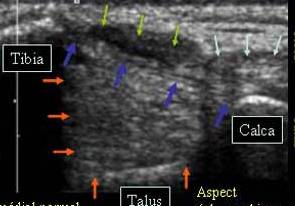

LIGAMENT COLATERAL MEDIAL NORMAL

Schema ligamentului colateral medial normal

Fascicol tibio talian anterior →

si tibio calcanean anterior →

Tendon tibial posterior →

Tendonul flexorului comun al degetelor →

Pozitia sondei _